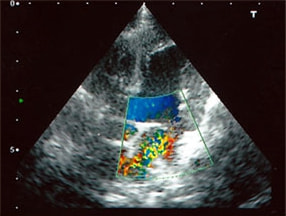

症例6:【ACVIM StageD ビーグル 10歳 去勢雄】

C:超音波 僧帽弁逆流のカラードップラー画像

左側胸壁心尖部領域を最強点とするLevine 5/6の収縮期性心雑音が聴取された。安静時にも咳が認められる。胸部レントゲン検査において重度の心拡大が及び肺水腫が認められた。超音波検査では、重度の僧帽弁閉鎖不全、三尖弁閉鎖不全が認められた。三尖弁逆流速度から肺高血圧症が示唆された。ACE阻害薬、ピモベンダン、硝酸イソソルビド徐放剤、ベラプロストナトリウム、利尿剤としてフロセミド及びスピロノラクトンを用いて治療を行っている。